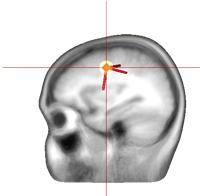

Forschung: Special: SchlaganfallrehabilitationIm Rahmen einer Kooperation zwischen Neurowissenschaftlern des Instituts für Neuroinformatik und Neurologen des Klinikums Bergmannsheil, beide in Bochum, wurde in den letzten Jahren ein Verfahren zur Leistungssteigerung des menschlichen Tastsinns entwickelt, die sensible Stimulation.  Bei diesem Verfahren (siehe passive Stimulation) werden kurzzeitig Impulse über die Handnerven in das Gehirn geleitet, um dort eine Reorganisation auszulösen, wie sie sonst nur durch intensives und häufig wiederholtes Training erreicht werden kann. Diese Stimulation, deren Leistungsfähigkeit mittlerweile an mehr als 1000 Probanden erprobt wurde, führt nicht nur zur einer Verbesserung des Tastsinns, sondern auch von haptischen und feinmotorischen Fähigkeiten.